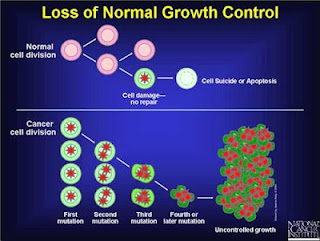

Even with the exception of anaerobic protists and fungi, it was believed until just recently that at least all multicellular eukaryotic (metazoan) organisms depended aerobic respiration for energy production. However, there are even metazoan exceptions. A 2010 study of the bottom of the Mediterranean Sea found three different animals that survive without using oxygen and therefore don’t have mitochondria.

These new loriciferans have hydrogenosomes instead of mitochondria, and produce ATP in the same ways as T. vaginalisand the other anaerobic eukaryotes. This is a completely new door being opened in biology, because the multicellular animals evolved after Earth turned from an anoxic environment to a place where oxygen was plentiful. It seems that even some of the more advanced organisms don’t have a problem reverting to more ancient systems if they find themselves in a place where they need it.